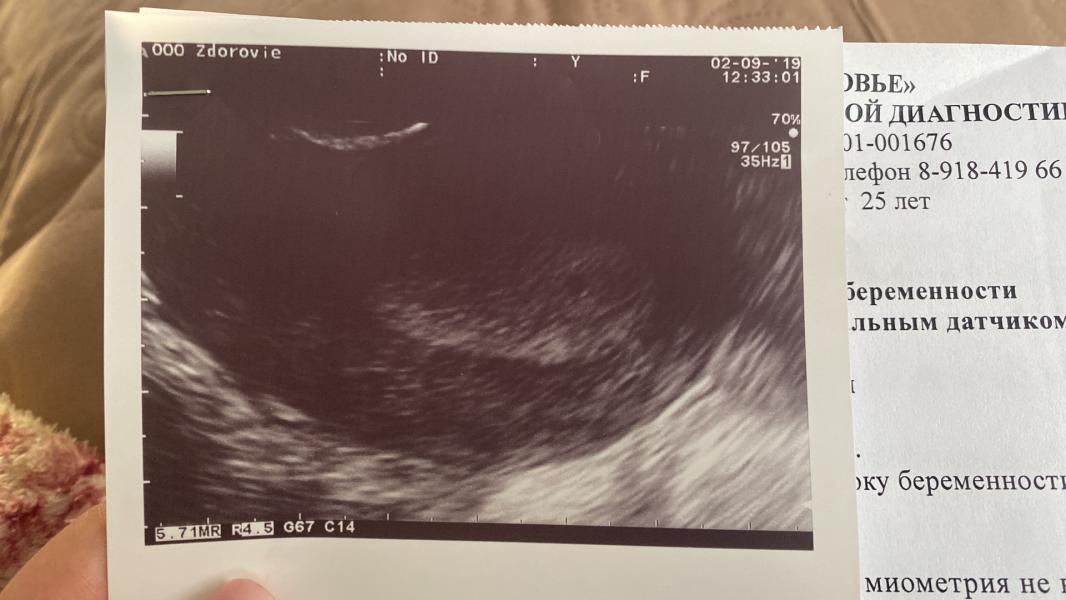

Сыну исполнилось 8 месяцев!❤️ у нас гв. Через 3 дня начал бросать грудь (ну понятное дело, что уже супчики, кашки и все такое) но все же…. Начал выплёвывать мое молочко🤦♀️ на сл.день пошла какая-то мазьня. Я бегом в поликлинику, мазки, хгч сказали сдать, хгч пришёл по нулям, с утра поехала сдавать повторно хгч, а вот в матке сюрприз❤️